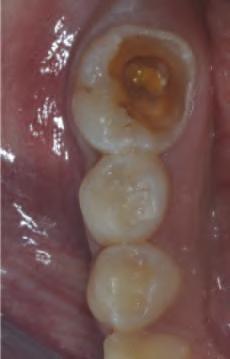

În zonele edentate cu d sponb l tate osoasă comprom să în d mens un le vert cale sau or zontale, mplantur le scurte ș /sau cu d ametru îngust sunt modal tăț alternat ve de tratament la procedur le de grefare osoasă pentru plasarea convenț onală (f g. 1, 2). Implantur le scurte (lung mea <10 mm) pot f plasate fără grefare osoasă vert cală. În general, lățmea mplantulu este cons derată ma mportantă decât lung mea acestu a pentru d s parea stresulu . Zona osulu crestal pr mește pres unea max mă, ar spre porț unea ap cală a mplantulu se

Figurile:

1. Utilizarea implanturilor scurte (lungime 6 mm) pentru a evita o augmentare cu grefă de sinus.

2. Utilizarea mai multor implanturi de dimensiuni mici, de tip monobloc, pentru a restaura o arcadă maxilară edentată îngustă fără grefare.